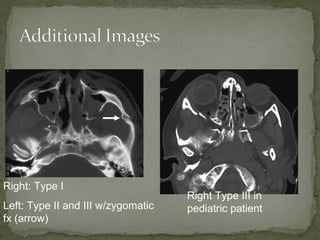

A 38-year-old man was found unconscious 40 yards from the scene of a motorcycle accident. He had obvious facial trauma including a midface fracture, severe facial edema, and blood in his oropharynx. His vital signs included a temperature of 98.6 F, heart rate of 120, respiratory rate of 12, and oxygen saturation of 90% on a nasal cannula with a blood pressure of 95/60. His Glasgow Coma Scale was 8. Imaging showed right type III and bilateral pterygoid fractures. He required intubation, ophthalmology consultation, and admission to the operating room for open reduction and internal fixation of his facial fractures.